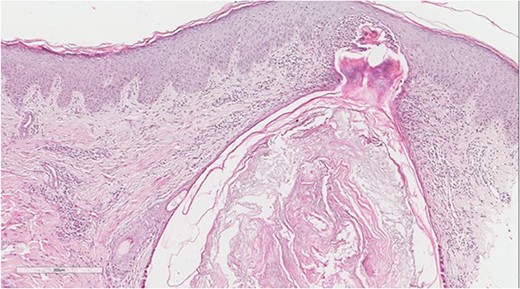

A 5 mm skin punch biopsy was also taken from the neck. Histopathology showed cystically dilated hair follicle with surrounding fibrosis and heavy inflammatory infiltrate and granulation tissue (Fig. 1), the inflammatory infiltrate is composed of lymphocytes, plasma cells, neutrophils and histiocytes (Fig. 2). The overall morphologic picture was suggestive of follicular occlusion syndrome (Fig. 3). A diagnosis of HS was made, and the patient was started on rifampin 600 mg OD and clindamycin 300 mg BID. A lipid panel was ordered as well and showed a triglyceride level of 1.99 mmol/L (0.7–1.7 mmol/L).

Perivascular lymphoplasmacytic infiltrate that is a common finding in HS.